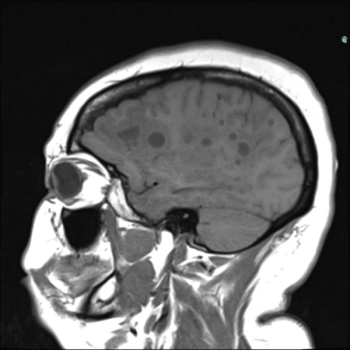

In a young patient with chronic seizures, what is the diagnosis?